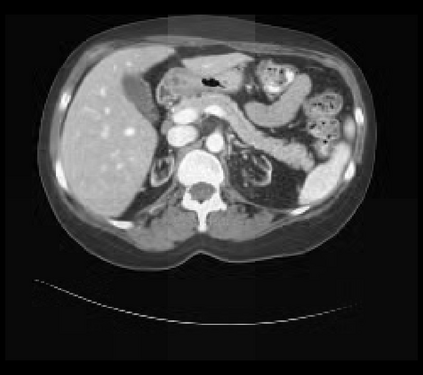

It is imperative to ensure the robustness of deep learning models in critical applications such as, healthcare. While recent advances in deep learning have improved the performance of volumetric medical image segmentation models, these models cannot be deployed for real-world applications immediately due to their vulnerability to adversarial attacks. We present a 3D frequency domain adversarial attack for volumetric medical image segmentation models and demonstrate its advantages over conventional input or voxel domain attacks. Using our proposed attack, we introduce a novel frequency domain adversarial training approach for optimizing a robust model against voxel and frequency domain attacks. Moreover, we propose frequency consistency loss to regulate our frequency domain adversarial training that achieves a better tradeoff between model's performance on clean and adversarial samples. Code is publicly available at https://github.com/asif-hanif/vafa.